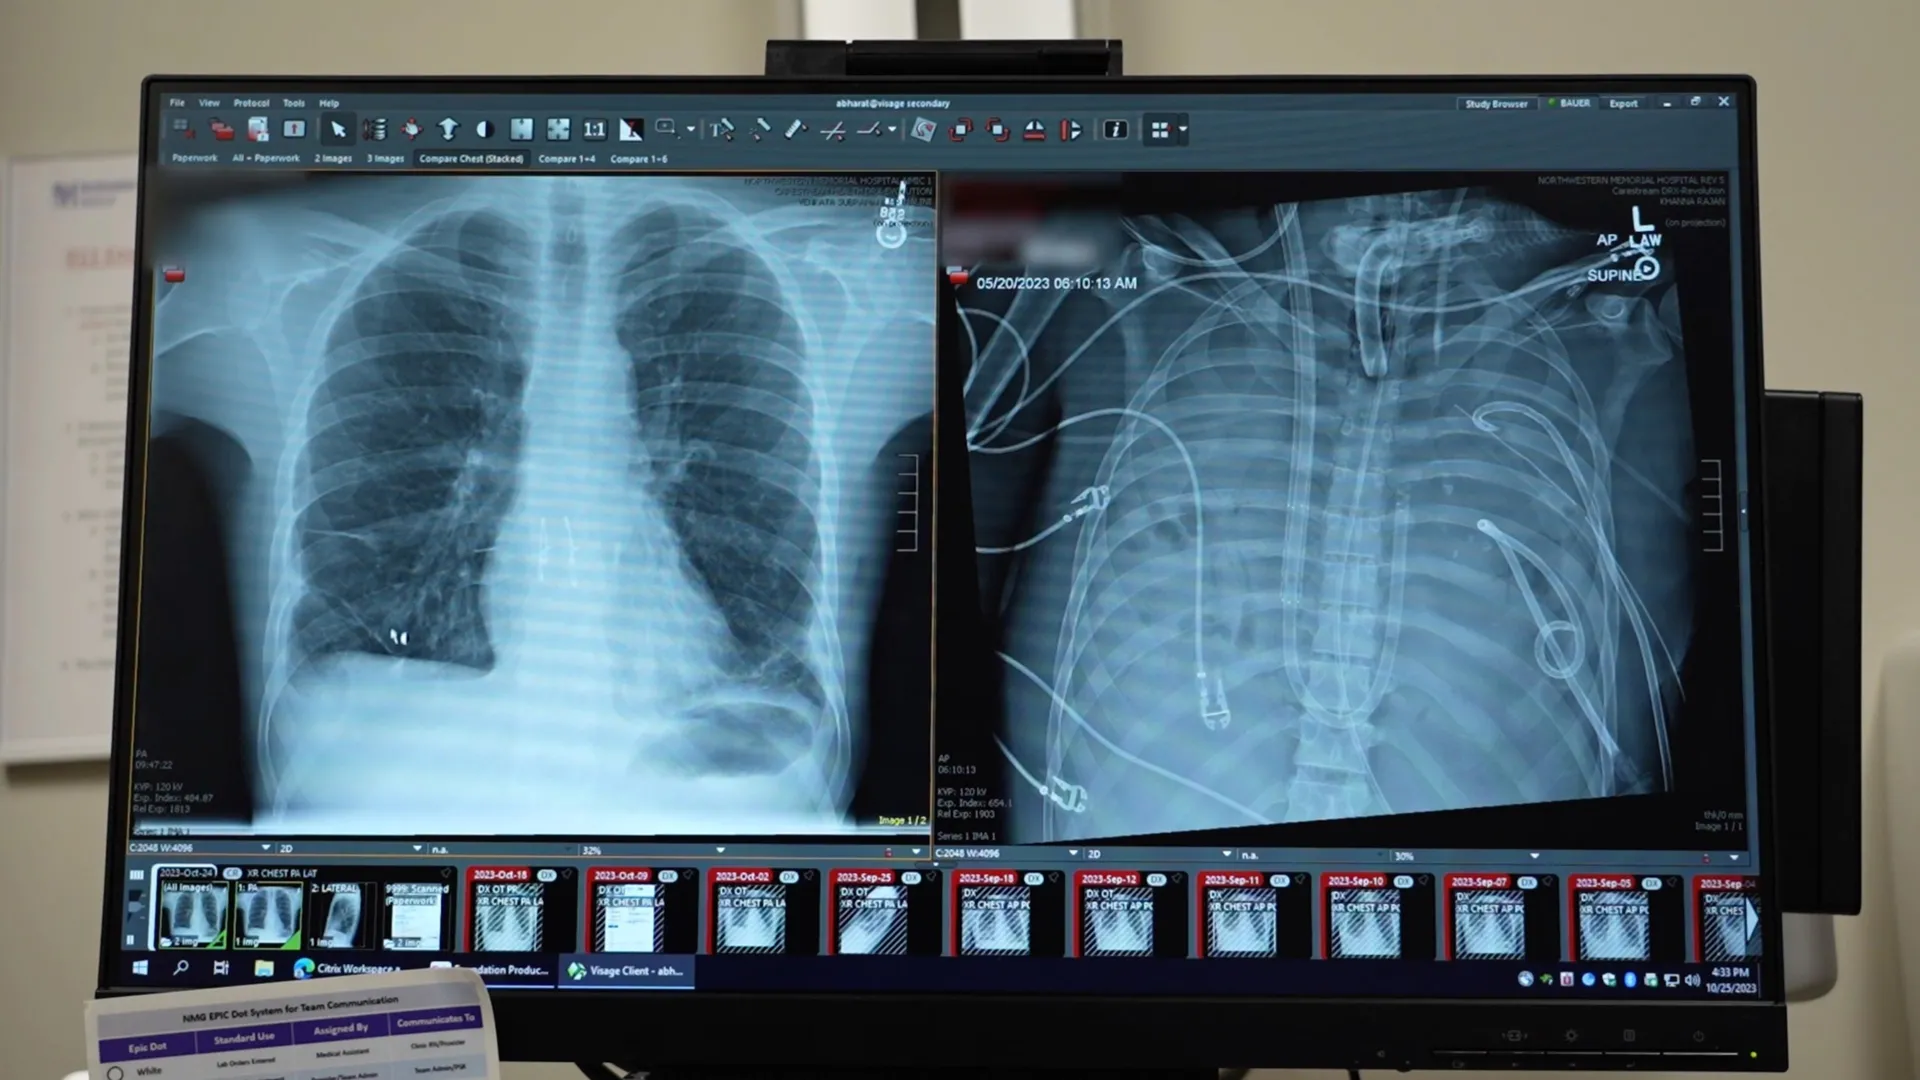

Согласно отчету хирургов из Северо-Западного университета (Northwestern University), опубликованному в журнале Med, зафиксирован уникальный случай выживания пациента после полного удаления обоих легких. Сообщается, что 33-летний мужчина провел 48 часов без органов дыхания, пока врачи боролись с тяжелейшей инфекцией, вызванной осложнениями после гриппа. По словам медиков, легкие пациента были настолько повреждены воспалением и бактериальной пневмонией, что стали источником заражения для всего организма.

Как поясняют авторы работы, единственным шансом на спасение пациента являлась двусторонняя трансплантация легких, однако тяжелое состояние не позволяло провести операцию незамедлительно. Медики приняли решение полностью удалить пораженные некрозом ткани, чтобы купировать дальнейшее распространение инфекции. На период отсутствия органов дыхание обеспечивала специальная система экстракорпоральной мембранной оксигенации («искусственное легкое»), которая насыщала кровь кислородом и удаляла углекислый газ, одновременно поддерживая работу сердца и почек.

Руководитель исследования Анкит Бхарат (Ankit Bharat) заявляет, что этот случай дает биологическое доказательство необратимости повреждений при тяжелом респираторном дистресс-синдроме. Спустя два дня после удаления легких были найдены донорские органы, и хирурги успешно провели пересадку. Сообщается, что спустя два года после операции пациент вернулся к нормальной жизни. По версии ученых, подобный подход может стать «мостом» к трансплантации для критически больных пациентов, которые ранее считались безнадежными.